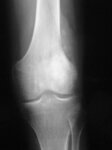

Conventional radiograph, anteroposterior view; poorly circumscribed, permeative lesion involving distal femoral metaphysis with mixed radiodense and radiolucent appearance; a large soft tissue mass with periosteal reaction is also present

Personal collections of Dr Michael J. Klein and Dr Luminita Rezeanu